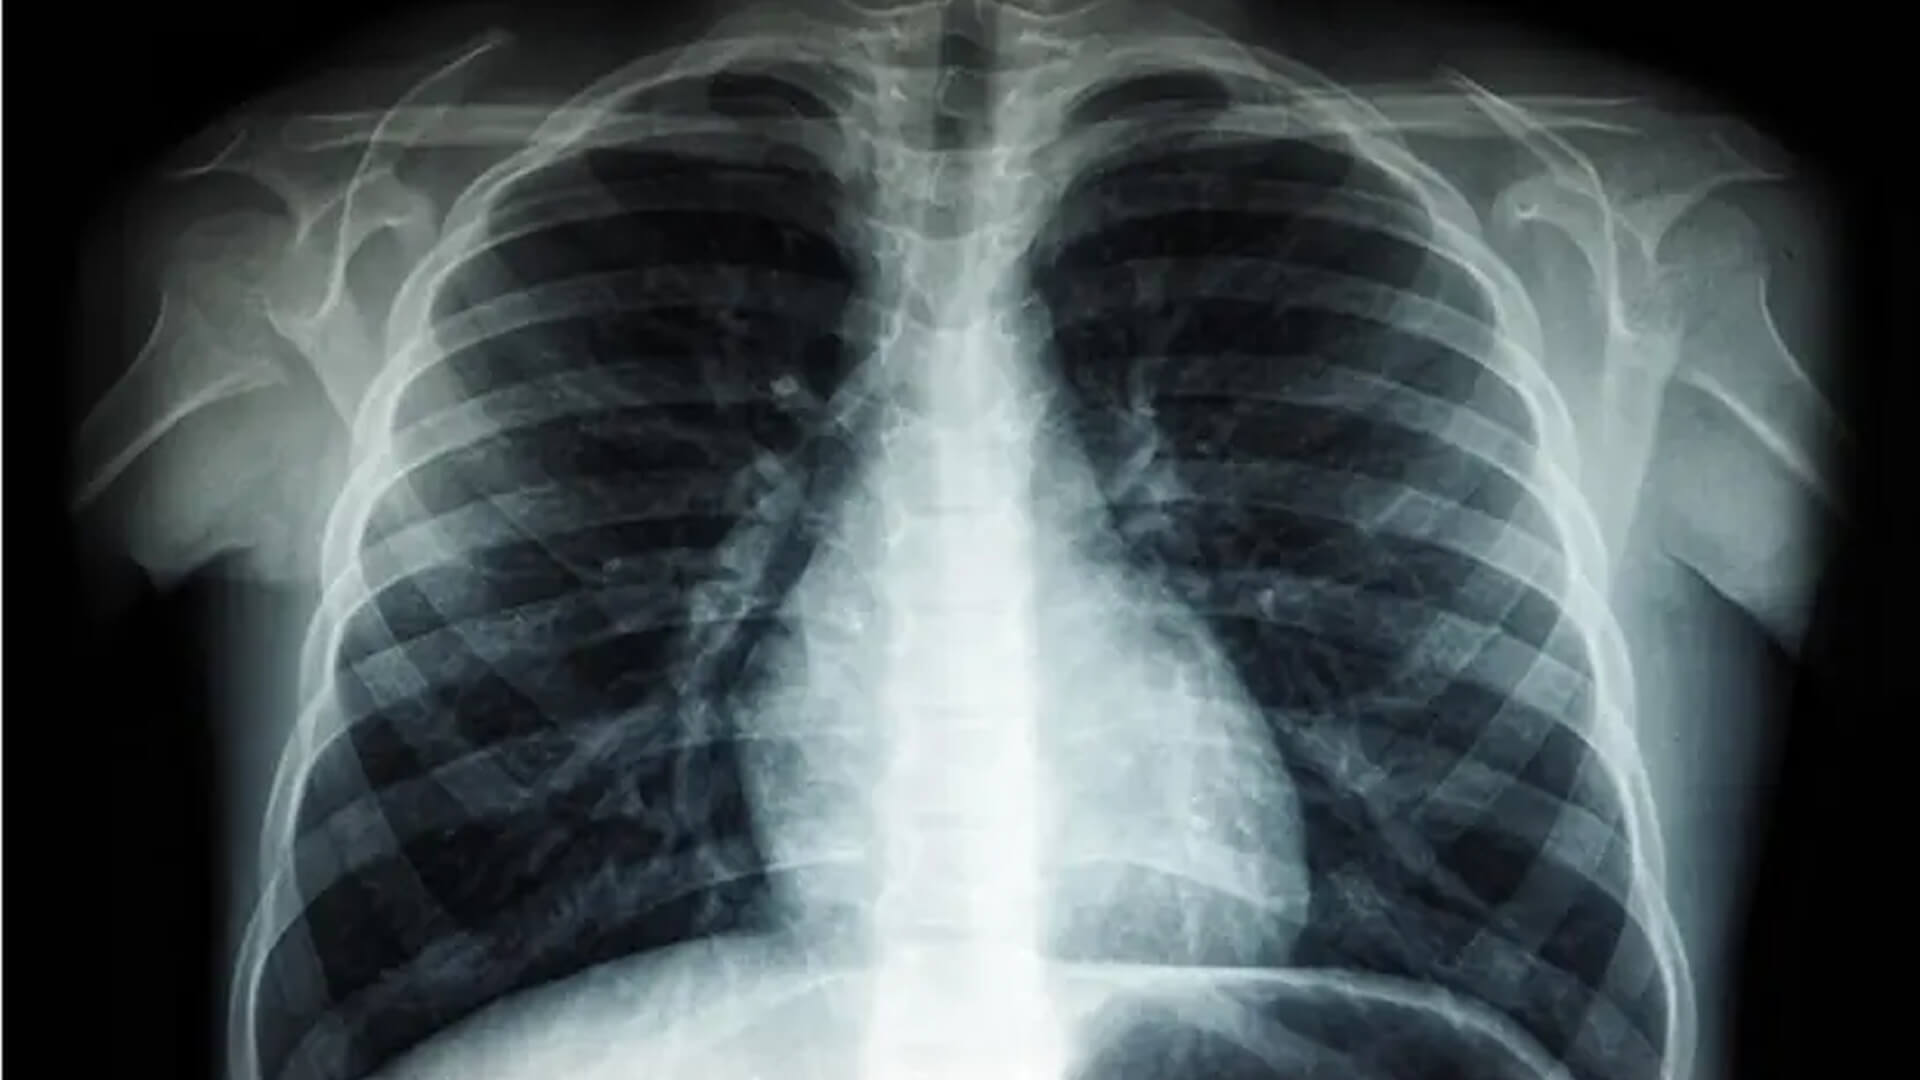

Your GP will usually do the initial examination. If a heart murmur is heard or they suspect you may have a problem with one of your valves your GP will refer you for an Echocardiogram (Echo) or directly to a cardiologist.

How is Aortic Stenosis diagnosed?

Aortic Stenosis can be diagnosed using several methods. These may include: